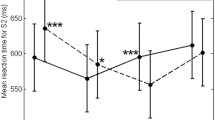

It could be ascertained by camera monitoring that all the subjects performed the lip protrusion task perfectly and symmetrically. The BOLD signals data analysis with Brain Voyager showed that the sensorimotor cortex was activated strongly and widely in all the subjects. No significant activation in Broca’s or Wernicke’s areas was observed. Table 1 shows the summary of the number of activated voxels in the sensorimotor cortex at a corrected P < 0.001 by the multiple comparison method, and the Talairach coordinates at the most active regions. In men, the results of individual data analysis revealed a larger number of activated voxels in the left sensorimotor cortex than that in the right, and there was a statistically significant difference in the number of activated voxels between in the left and the right side (Wilcoxon signed rank test, P = 0.0051) (Fig. 1). On the other hand, no significant difference was found between the left and right side in women (Fig. 2). There was a statistically significant difference in interaction between the hemisphere and sex (Two-factor factorial ANOVA, P = 0.041) and multiple comparison test showed statistically significant differences between “men and right” and “men and left”, and between “men and left” and “women and left” (Fisher’s PLSD method, P = 0.018, 0.026, respectively). The results of group data analyses indicated bilateral strong activation of the sensorimotor cortex during lip protrusion at an uncorrected P < 3.1294 e−12 level (corrected P-values could not be seen in the statistical maps; i.e, P < 0.000) by the multiple comparison method (Bonferroni’s correction) (Figs. 3 and 4). In general, the cluster size of the activated area in the group data analysis was larger than that in the individual data analysis because of the averaging of each individual data set. The areas of activation on the left side were larger than those on the right side in men, though no significant laterality was observed in women. Activation in the bilateral supplementary motor cortex and cerebellum was also observed, but no laterality was found (Wilcoxon signed rank test, P > 0.05, respectively). Detailed analysis of the averaged time-course of changes in the BOLD responses for the ROIs in the sensorimotor cortex revealed that the peak %BOLD signal in the left sensorimotor cortex was approximately twice as large as that in the right in the male group (Fig. 3), although no laterality was found in the female group (Fig. 4). In detail, the peak value of the percent changes in BOLD signals for the right sensorimotor cortex was approximately 0.5, whereas it was 1.2 for the left in men. In a GLM (multi-study, multi-subject) analysis, the left primary sensory area was significantly activated (yellow), though the right one was not activated (right, Fig. 5). A cluster center of spatial gravity was evaluated at the Talairach coordinate sets (−51, −22, 36) corresponding to the primary sensory area related to the face area. On the other hand, green regions were also activated as brain regions where female activation was greater than male. A cluster center of the left hemisphere green region near the yellow one was evaluated at the Talairach coordinate sets (−40, −21, 42) and that of the right one was (47, −19, 44). Statistical analysis of data in the group study and the male and female characteristics (mean age, laterality quotient, past history of facial nerve diseases or cerebrovascular diseases) are shown in Table 2. There was no statistically significant difference in the R/L amplitude ratio of the facial muscle action potential between men and women as shown in Table 2.

Activation maps and time courses of activation in men during lip protrusion. Above. Activation maps were overlaid on coronal anatomical images at the setting of the statistical max value point. Below. Averaged time-course of changes in the BOLD responses for the regions of interest in the right and the left sensorimotor cortex. The primary sensorimotor cortex is significantly activated bilaterally and the area of activation on the left side is larger than that on the right side. The peak value of the percent changes in BOLD signals for the right sensorimotor cortex is approximately 0.5, although that for the left is 1.2. ROIs have been placed on the right (upper left) and the left (upper right) primary sensorimotor cortex as shown by the red cross. (Error bars indicate standard error)

Activation maps and time courses of activation in women during lip protrusion. Above. Activation maps were overlaid on coronal anatomical images at the setting of the statistical max value point. Below. Averaged time-course of changes in the BOLD responses for the regions of interest in the right and the left sensorimotor cortex. The primary sensorimotor cortex is activated bilaterally and almost equally. The peak value of the percent changes in BOLD signals for the right and left ensorimotor cortex is approximately 0.9, respectively. ROIs have been placed on the right (upper left) and the left (upper right) primary sensorimotor cortex as shown by the red cross. (Error bars indicate standard error)